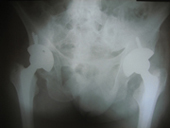

Arthriis of both hips pre op Arthriis of both hips post op Arthritis knee valgus deformity pre op Arthritis knee valgus deformity post op

30 years old lady presented with complaint of pain right hip since 7 yrs and getting worse since 1 month. She is unable to walk and stand for a long time.

On examination she is having a painful limp, shortening of right lower limb, her hip movements are restricted and painful.

Xray showed evidence of old perthes disease and secondary osteoarthritis of right hip.

In view of her young age , an uncemented Total Hip Replacement was carried out.